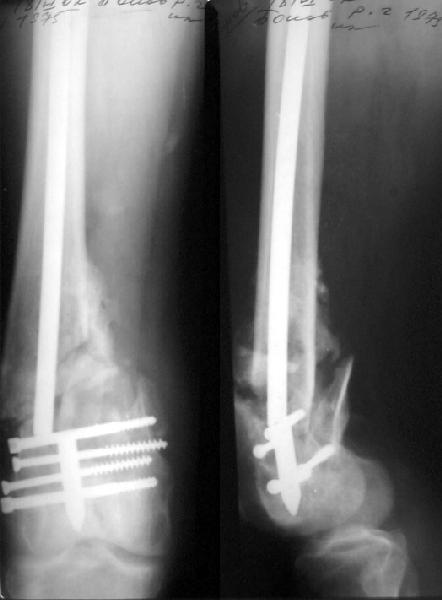

Пациент 27 лет оперирован 2.04.02 через 2 недели после открытого перелома дистального отдела бедренной кости (1 снимок).

Сделан антеградный закрытый интрамедуллярный остеосинтез UFN 11 мм (2 снимок). Вторая нога была ампутирована по месту первичного поступления. Для возможности ранней нагрузки использованы блокирующие винты 6 мм, для чего дистальные отверстия были рассверлены. К двум месяцам начал вставать на костыли, до того занимался разработкой движений в колене. Эти циклические движения в сочетании с тем, что зона концентрации нагрузок приходилась как раз на уровень отверстия, и что перелом открытый и тяжелый и не успел прочно схватиться, привели к перелому стержня 8 июня (3 снимок). Вчера госпитализировали. Такое осложнение у нас впервые. Пока думаем про реостесинтез - вытолкнуть дистальный отломок через дистально, да и через то же отверстие заштифтовать ретроградно. Или наложить аппарат после удаления центрального отломка стержня, если что-то не будет получаться. Или подумать про пластинку? Заранее спасибо.